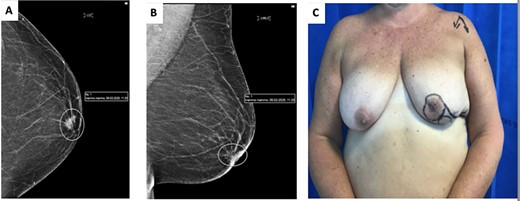

(A) images showing preoperative markings of modified Grisotti flap. Note the short nipple to IMF crease length, which would significantly shorten further if a standard Grisotti technique were undertaken. (B) En bloc resection of NAC and tumour creating a significant defect. (C) Harvesting of modified Grisotti flap with de-epithelialization of the skin surrounding the flap with preservation of the medial triangle skin (delimitated superiorly by the areola and inferiorly by disc of skin to be rotated).

The NAC–IMF distance in this patient was measured pre-operatively as 6 cm (Fig. 2A). Since the traditional flap markings (Fig. 4B) (use of a 4 cm disc of skin to form the neo-areola, based at the 6 o’clock position) would have resulted in an unacceptable shortening of the NAC–IMF distance, the technique was modified as described below.

Markings were performed preoperatively. The diameter of the skin disc used to form the neo-areola was reduced to a 3 cm instead of the usual 4 cm and was positioned in the lower-outer quadrant of the breast rather than at the standard 6 o’clock position (Fig. 2A).

Following en bloc excision of NAC and the tumour (Fig. 2B), the medial triangle of the skin (delimitated superiorly by the areola and inferiorly by the disc of skin to be rotated) was preserved to avoid creating a ‘teardrop’ shape of the new areola at the time of closure as described by Della Rovere et al. [3] (Fig. 2C).